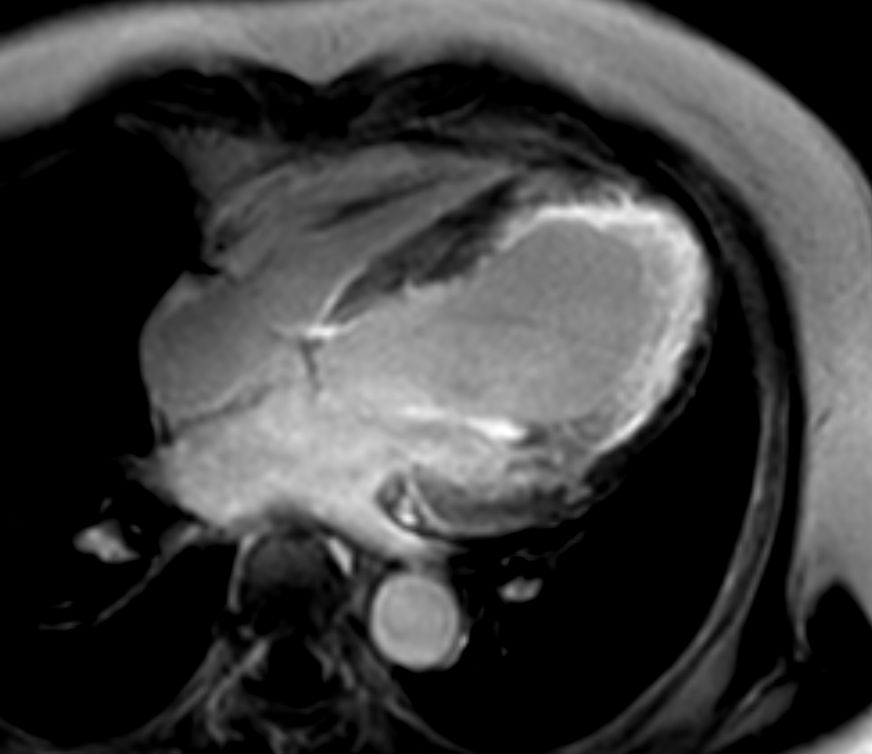

Short axis view T2w Black Blood